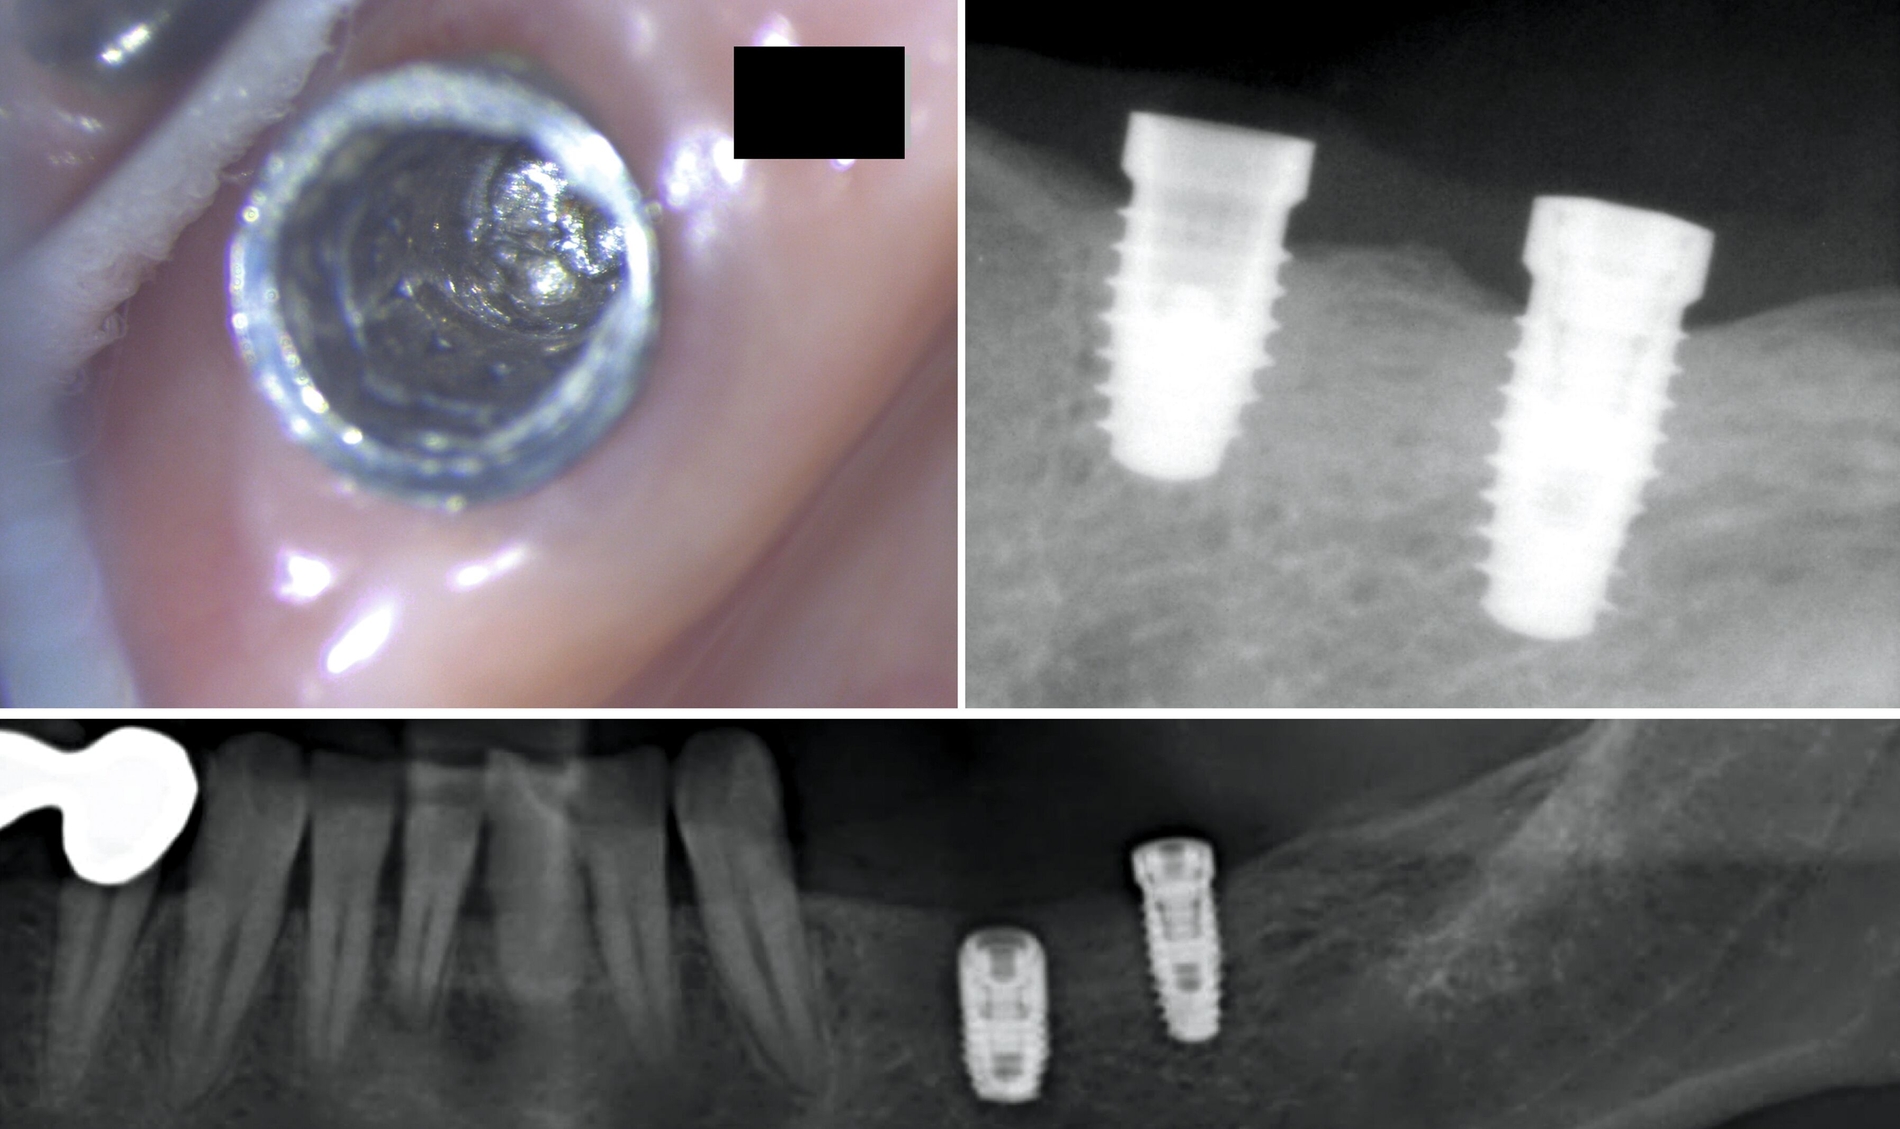

In diesem Fall war das Abutment in regio 36 etwa sieben Jahre nach der prothetischen Versorgung frakturiert. Beim Versuch, die Krone zu entfernen, kam es zusätzlich zur Separation der Befestigungsschraube. Beide Fragmente konnten mithilfe eines systemspezifischen Spezialwerkzeugsatzes (zum Beispiel Reparaturset von Ankylos, Dentsply Sirona) entfernt werden.

Das herstellerseitig empfohlene Vorgehen sieht vor, das Abutmentfragment zentral mit einem runden Bohrer oder Diamanten (Ø 1,2–1,4 mm) anzukörnen. Anschließend erfolgt die Bohrung mit einem speziellen Kernlochbohrer (Ø 1,8 mm, Tiefe circa 3 mm) bei 1800 U/min und unter Kühlung. Ein passender Extraktionsstift wird eingeschraubt und das Schraubenfragment mithilfe eines Ausdrehers entfernt. Für verbliebene Gewindehülsen stehen spezielle Ausdrehinstrumente zur Verfügung; in schwierigeren Fällen kann zusätzlich ein Spiralbohrer (1,4 mm) zum Einsatz kommen. Der finale Schritt besteht in der Nachbearbeitung des Innengewindes mit einem Gewindeschneider (M1,8). Zur Minimierung des Friktionswiderstands kann die Verwendung eines Gleitmittels (zum Beispiel Vaseline) hilfreich sein. Ein verkantungsfreies Arbeiten ist essenziell, um Instrumentenbruch und Implantatverlust zu vermeiden. Die radiologische Darstellung des Bruchs sowie die Situation nach Entfernung der Komponenten sind in den Abbildungen 3 und 4 dokumentiert.

In diesem Fall kam es durch die Verwendung nicht originaler Komponenten zur Befestigung eines Langzeitprovisoriums zu einer Abnutzung des Konnektors im Schraubenkopf. Beim Versuch, das Provisorium im Rahmen der definitiven Abformung zu entfernen, ließ sich das Abutment nicht mehr lösen (Abbildung 5). Nach Abnahme des Kunststoffteils wurde zunächst versucht, eine Rille zur Aufnahme eines schlitzförmigen Schraubendrehers mithilfe eines kleinen Rundbohrers (zum Beispiel EKR-Bohrer) zu fräsen (Abbildung 5). Aufgrund der verbliebenen Grate war jedoch keine effektive Kraftübertragung möglich. Schließlich erfolgte eine zirkuläre Entgratung des Schraubenkopfs mit einem diamantierten Ultraschallinstrument gegen den Uhrzeigersinn. In der Folge ließ sich die Schraube durch kontinuierliche Linksdrehung erfolgreich aus dem Implantat entfernen (Abbildung 6).